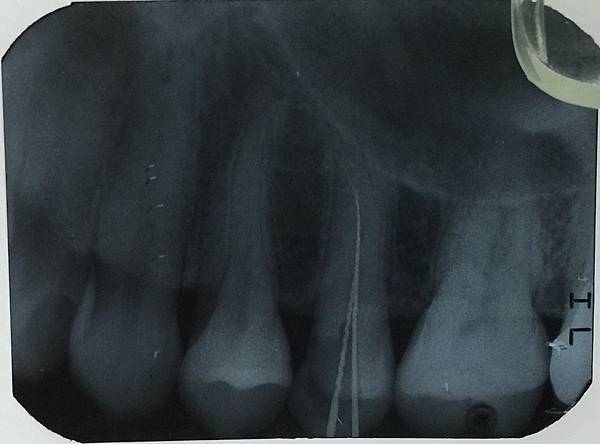

欣美牙醫分享住國外的Y小姐病例來說明:

在洗牙過程發現牙齒有變色與潛在蛀牙

所以拍一張X光片發現:

左上第二小臼齒有一個大蛀牙

因為蛀在兩個牙齒交界所以外觀上看不到

對照上一張圖來看更容易了解